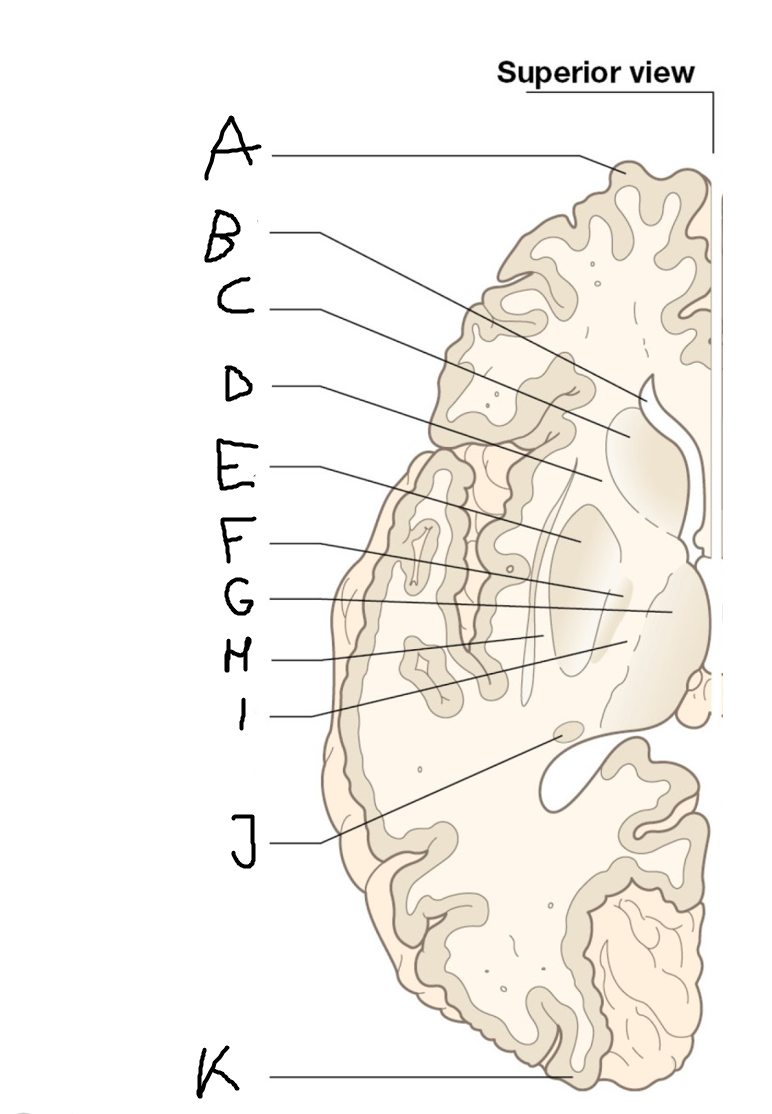

internal capsule (posterior limb)

B

anterior horn of lateral ventricle

C

head of caudate nucleus

D

internal capsule (anterior limb)

E

putamen

F

globus pallidus

G

Thalamus

H

External capsule

I

internal capsule (posterior limb)

J

tail of caudate nucleus